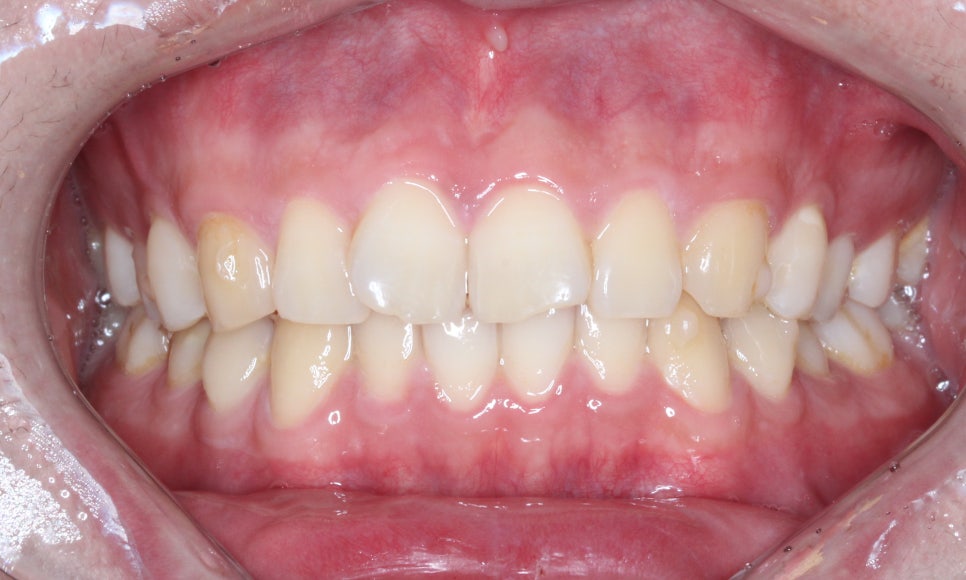

나비치아교정! 15개월만에 빠른 교정 by.투디치과(2D치과)

정면에서 보아도 확실히

교정 전과 달리 정돈된 모습이네요!

문제였던 11번, 12번 치아 역시

V자 형태가 아닌 부드러운 곡선을

띠게 되었습니다!